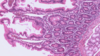

Bile canaliculi - hepatocyte cell membrane (arrowheads) are clearly evidence in this photomicrograph. Note that in fortuitous sections, bile canaliculi (arrows) are recognizable. These bile canaliculi are small intercellular spaces through which bile flows to the periphery of the lobule. Human Liver.

Bile canaliculi - Bile is secreted into bile canaliculi (BC). These channels are formed by the retraction of

the plasma membranes (arrows) of the hepatocytes to produce an open space between adjacent cells. Thus, bile canaliculi are not channels lined by a cell population distinct

from hypatocytes, but are an anastomosing series of tunnels lined y the hepatocytes themselves. Microvilli from the surface of the hepatocytes that form the bile canaliculus entre the channel. Tight junctions (arrowheads) between the hepatocytes seal off the area and prevent leakage of bile into the intercellular spaces.